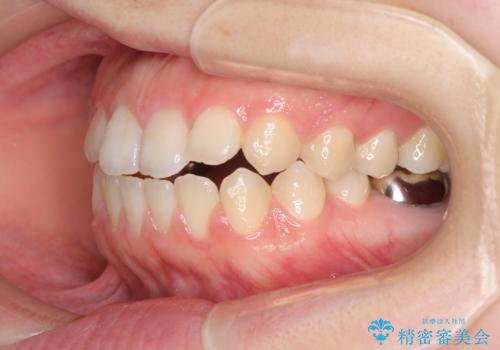

- 矯正装置

- 審美装置

- 口元の膨らみが気になるとのことで来院された患者様です。

非抜歯で口元の突出感を少し改善させる治療も提案しましたが、最大限口元を引っ込めたいとのことでした。

上下左右第一小臼歯4本を抜歯し、ワイヤー装置により矯正治療を行うこととしました。

治療は順調に進み、予定された期間で終了することができました。

装置除去後には、スッキリとした口元となり、大変満足していただきました。